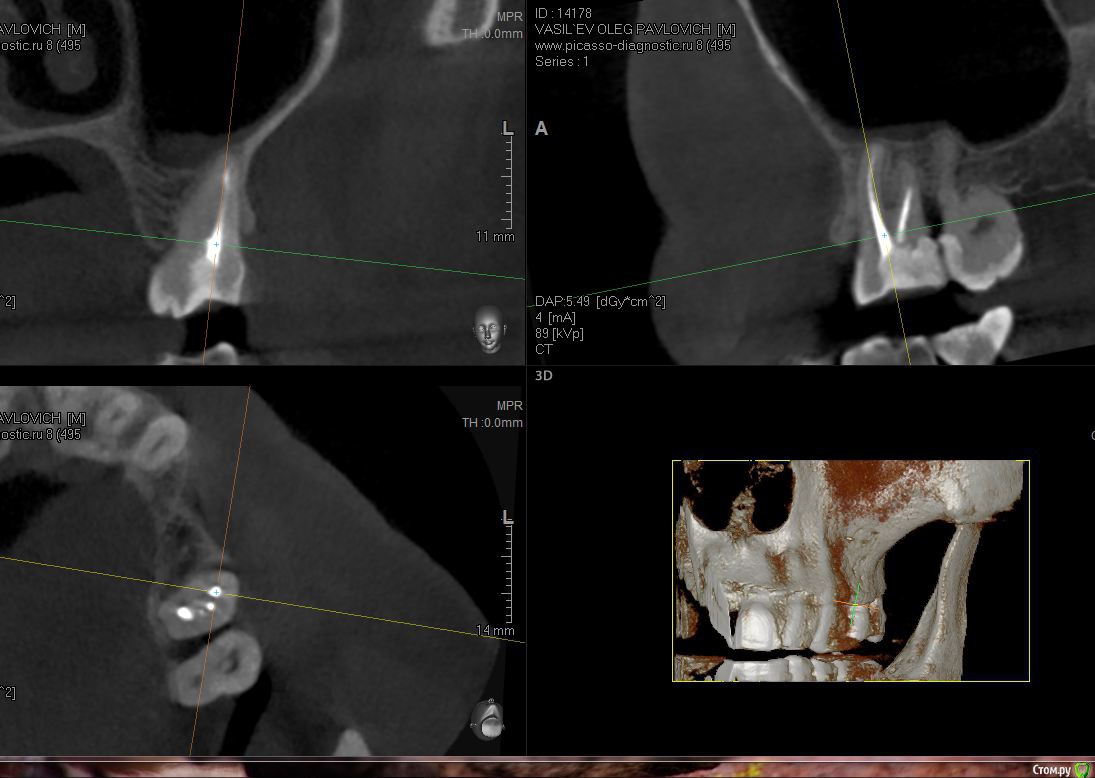

sugaka30 Опубликовано 22 января, 2017 Автор Поделиться Опубликовано 22 января, 2017 Проконсультируйте пожалуйста по этим срезам А то местный хирург не может понять что не так Ссылка на комментарий

sugaka30 Опубликовано 22 января, 2017 Автор Поделиться Опубликовано 22 января, 2017 Кт https://yadi.sk/mail/?hash=6%2BYypIPs7jLhymGB5GElIUtAs%2Fe5etH%2BeXj7hjHSjAc%3D Ссылка на комментарий

St. Опубликовано 22 января, 2017 Поделиться Опубликовано 22 января, 2017 Скрины кт в обл леченного зуба Ссылка на комментарий

sugaka30 Опубликовано 23 января, 2017 Автор Поделиться Опубликовано 23 января, 2017 Скрины кт в обл леченного зубаСпасибо Вам большое Вот еще бы кто объяснил что мне с этим делать Ссылка на комментарий